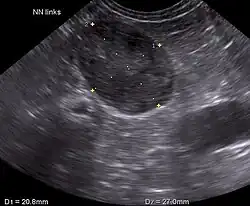

Ultrasonography, CT scans, and MRI are used to identify any abnormality in the pituitary or adrenal gland. This helps diagnose if the patient has pituitary-dependent Cushing's or adrenal-dependent Cushing's.[2]

Hamsters

Blood tests are not always practical for hamsters due to their small size; abdominal ultrasounds can be used to show adrenal gland enlargement.[3]